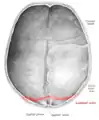

Lambdoid suture

The lambdoid suture (or lambdoidal suture) is a dense, fibrous connective tissue joint on the posterior aspect of the skull that connects the parietal bones with the occipital bone. It is continuous with the occipitomastoid suture.

![]() Lambdoid suture (shown in red line) | |

The lambdoid suture is between the paired parietal bones and the occipital bone of the skull. It runs from the asterion on each side.

The lambdoid suture is named due to its uppercase lambda-like shape.